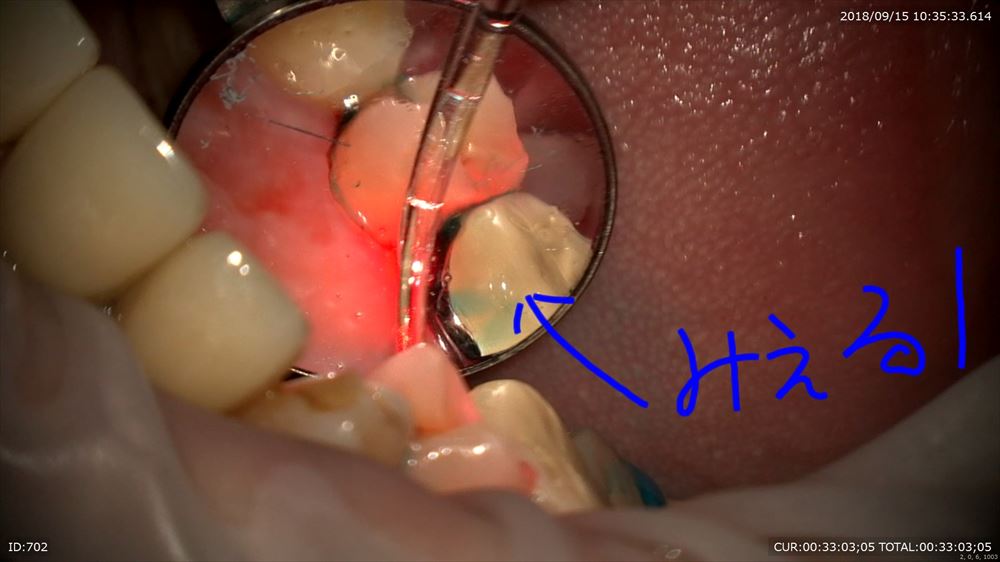

なんとここは右上のブリッジ下!!こんなに見える。6mmのポケット。

歯茎をどかしているのが解ると思います。切らないから痛くない。歯茎が下がらない。